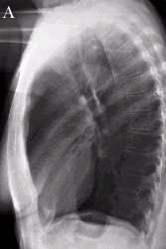

lateral chest

what lateral view would you get for a left sided lesion

a left lateral view